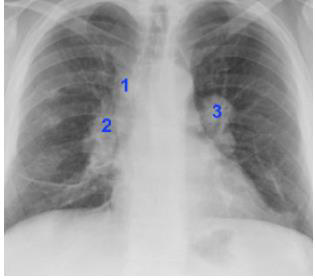

Sobre a radiografia torácica, o sinal do 1-2-3 está relacionado à linfonodopatia da sarcoidose nas regiões: